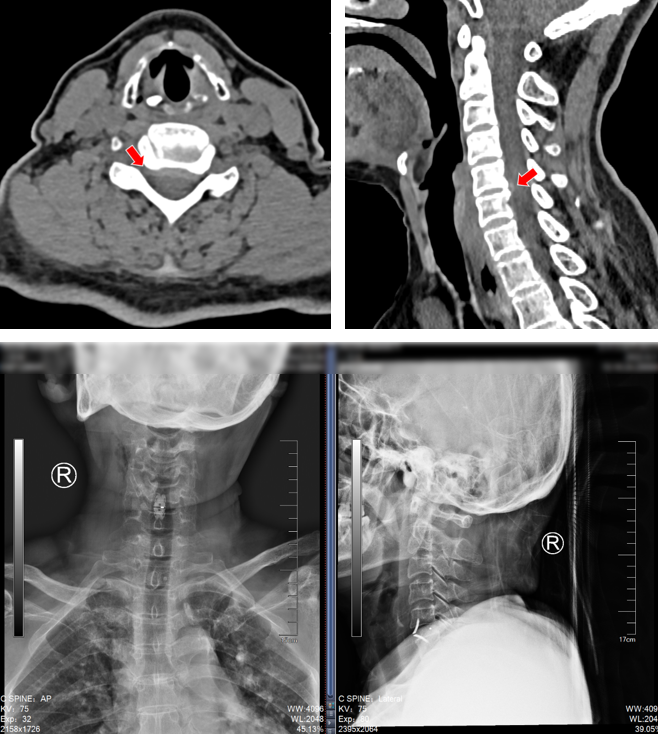

无独有偶,我院骨科还为一对姐弟完成了一组颈椎后路手术。姐弟俩吕艳、吕飞(化名)均患有“颈椎后纵韧带骨化症”。弟弟吕飞今年40岁,是位企业白领。别看他年龄不大,其实已多年饱受颈椎病之苦。由于长期伏案工作,这些年他常常感觉自己四肢乏力,走路像踩在棉花上一般,像系纽扣、写字这样的活动也逐渐无法完成,这让他很是着急。通过亲友介绍,他找到姜为民主任寻求帮助,姜主任在仔细的查体和阅片后,判断吕飞的颈椎后纵韧带骨化节段多,症状重,应当尽早手术,解除对脊髓的压迫。

(颈椎CT提示患者C3-6椎体后纵韧带骨化明显,椎管狭窄显著)

(颈椎术后X片:C3-6椎管扩大成形术后)

就在吕飞出院的当天,另一位症状相似的脊髓型颈椎病患者吕艳也来办理了住院手续。原来她是吕飞的亲姐姐,今年46岁。姐弟俩的症状和影像学表现都几乎相同,可见颈椎后纵韧带骨化确有一定的家族遗传倾向。吕艳告诉我们,他们姐弟这些年看过不少医生,都建议尽早手术,但因为听说颈椎手术风险极高,所以一直都选择“拖字诀”处理。这次吕飞的手术效果,给了她极大的信心和勇气,她毫不犹豫地也选择来做手术。

(姐姐的颈椎CT显示她的颈椎椎体同样存在明显的后纵韧带骨化,与弟弟不同的是,她的韧带骨化程度更严重)

(吕姐的接受的手术与吕弟一样,C3~6椎管扩大成形术。)